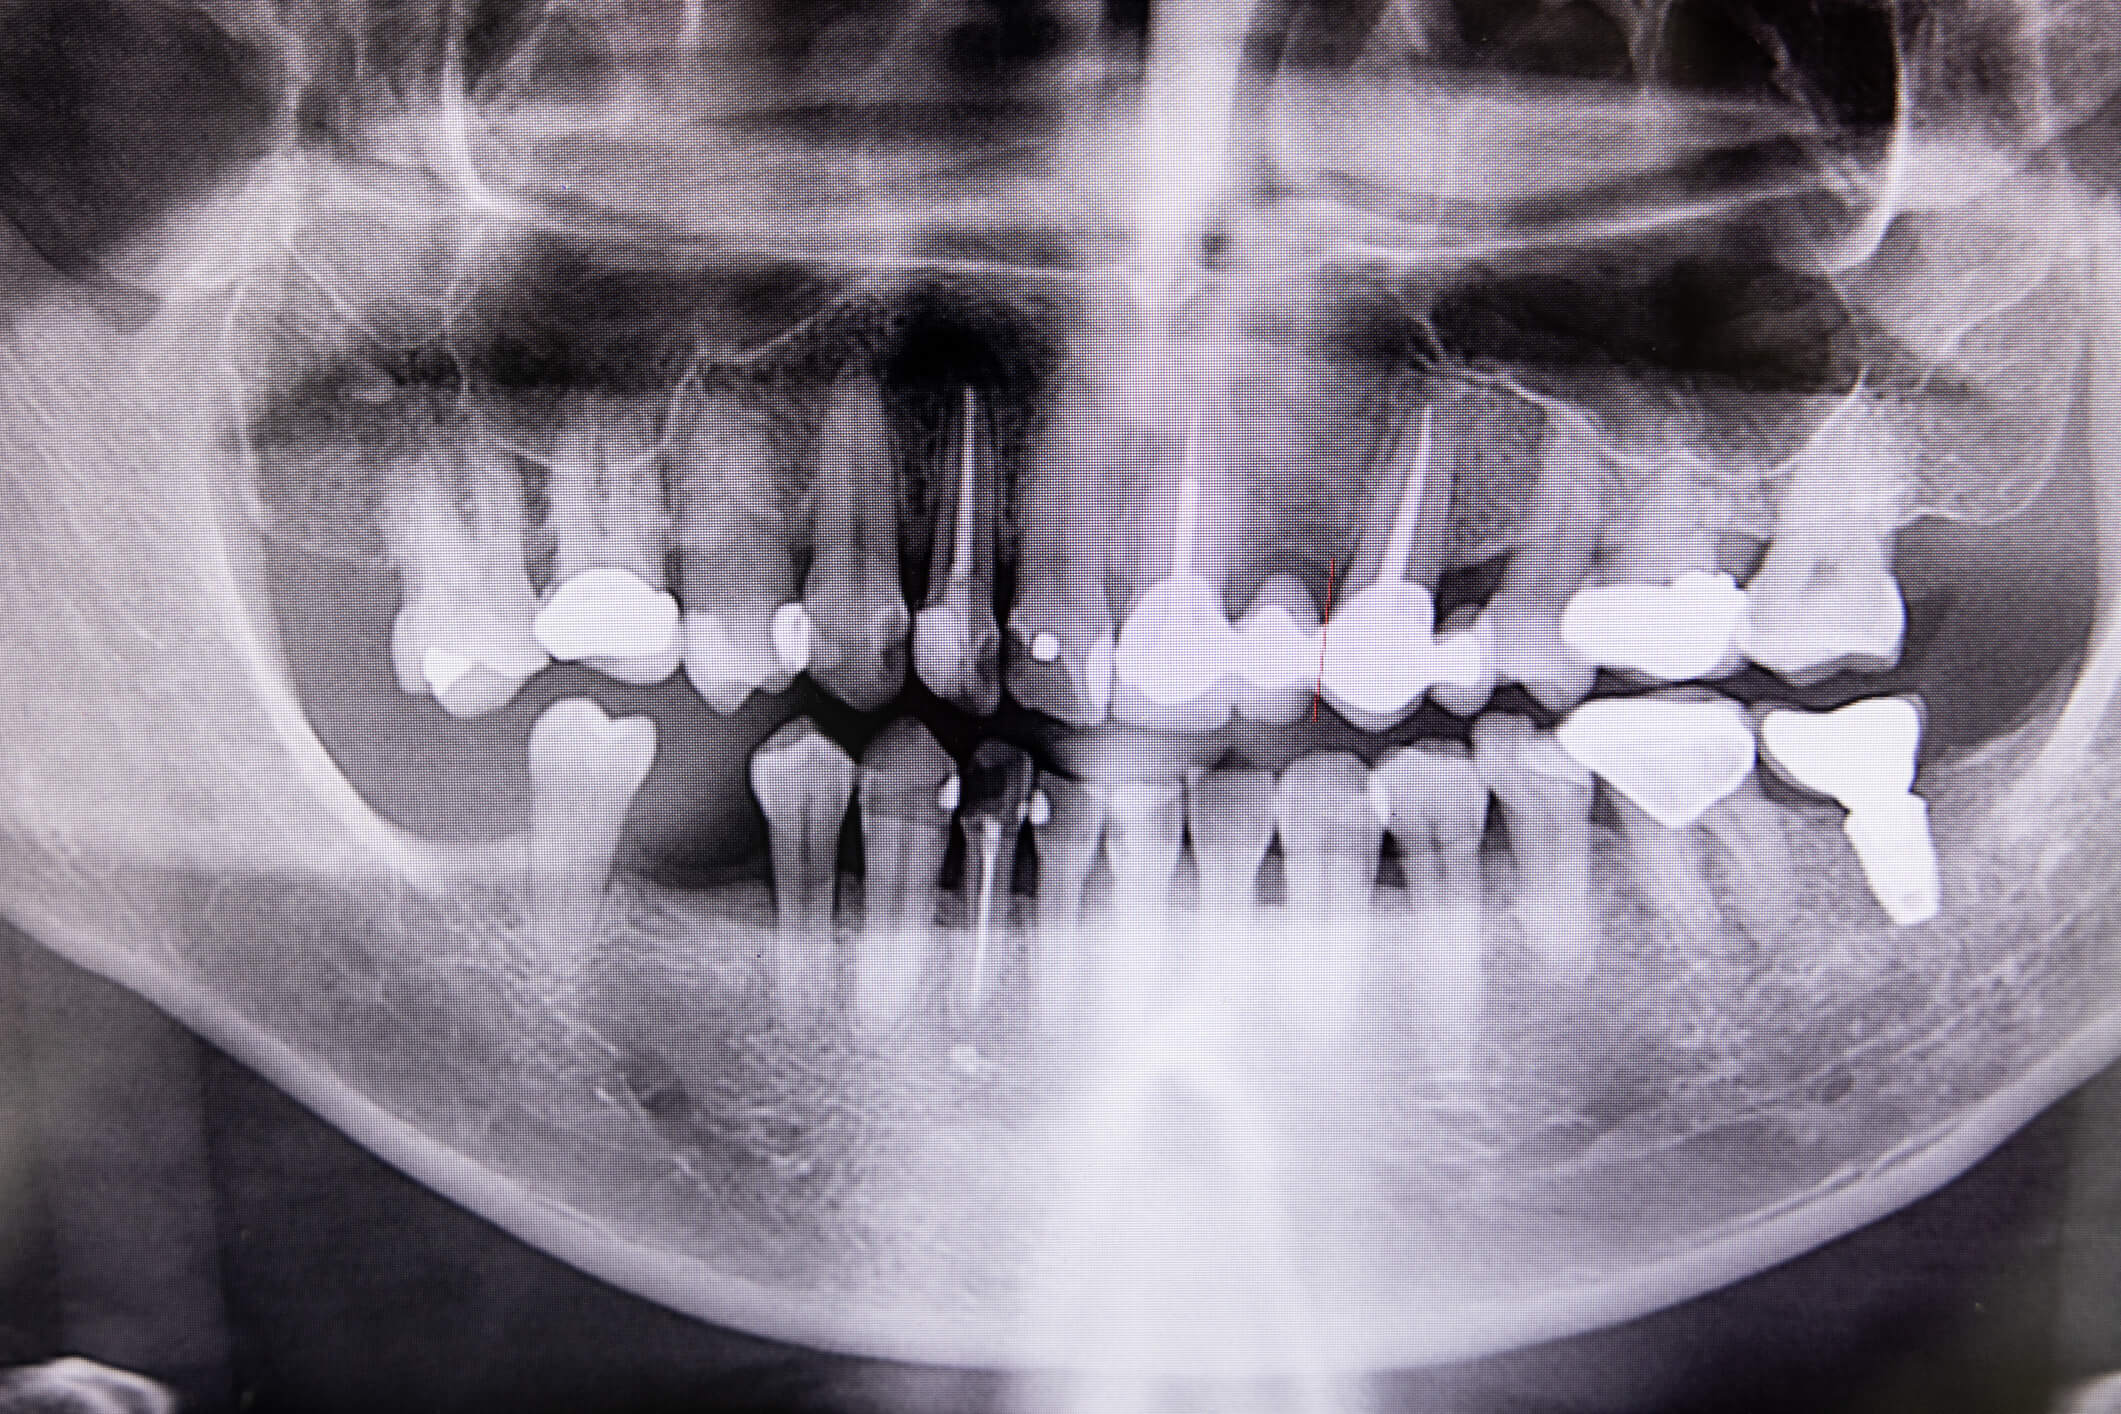

Root canal treatment, also known as endodontic therapy, is a dental procedure designed to save a severely damaged or infected tooth. When the innermost part of a tooth, called the pulp, becomes infected or inflamed due to deep decay, trauma, or repeated dental procedures, a root canal is necessary to remove the infected pulp and save the tooth from extraction. The procedure involves cleaning, disinfecting, and sealing the tooth to prevent further infection.

At Mackay Family Dental, we specialize in providing effective and comfortable root canal treatment. Our dental professionals will begin by examining your tooth and assessing the extent of the infection. The procedure is performed under local anesthesia to ensure your comfort. We will carefully remove the infected pulp, clean the root canals, and seal the tooth with a filling material. In some cases, a dental crown may be recommended to protect and strengthen the treated tooth.